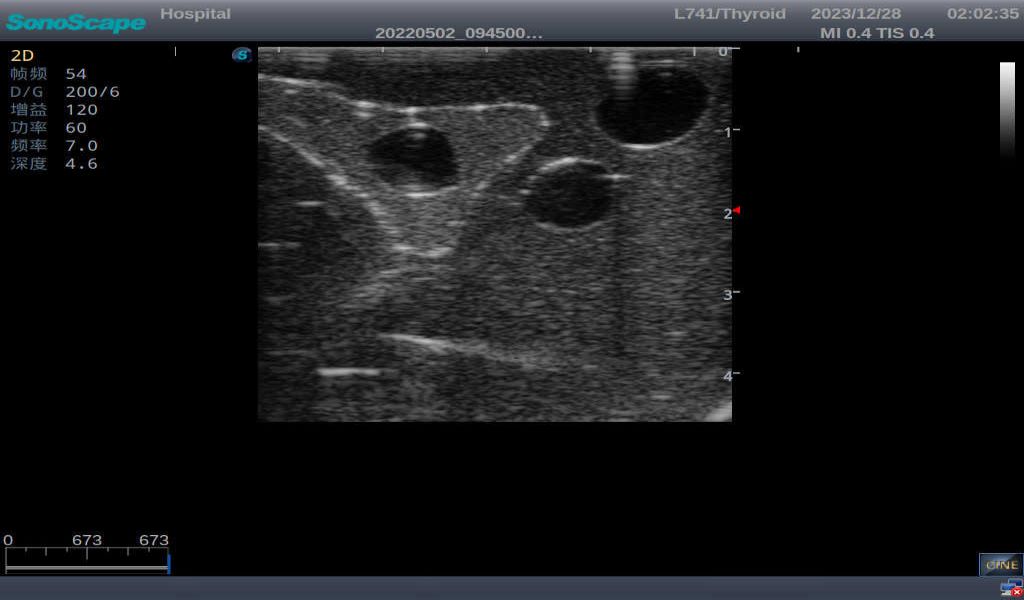

Thyroid Ultrasound Training Model

ModelTYE1595

This product has true-to-life male torso including head, neck, shoulder and upper chest. It serves as an excellent teaching tool for identification of various types of normal thyroid, thyroid adenoma, thyroid cancer, nodular goiter, thyroid cyst and training on proper thyroid scanning techniques.

3)       It comes with four (4) thyroid modules and can show five (5) ultrasonic images: normal thyroid, thyroid adenoma, thyroid cancer, nodular goiter, thyroid cyst

Normal thyroid with homogeneous parenchymal echo and well-defined capsule

Thyroid adenoma with well-defined border and smooth uniform halo

Thyroid cancer with irregular mass, unclear border, uneven internal echo or calcification strong echoes

Nodular goiter with irregular border and varying sizes of low echo, isoechoic, or high echo nodules

Thyroid cyst, which fluid area, dark and echo-free area can be seen